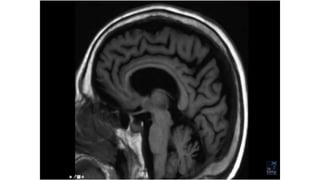

Slicing

7

Sagittal[s-s] Coronal[A-P] Axial[S-I]

Side view Front view Bottom up view

8

9

Imaging planes

10